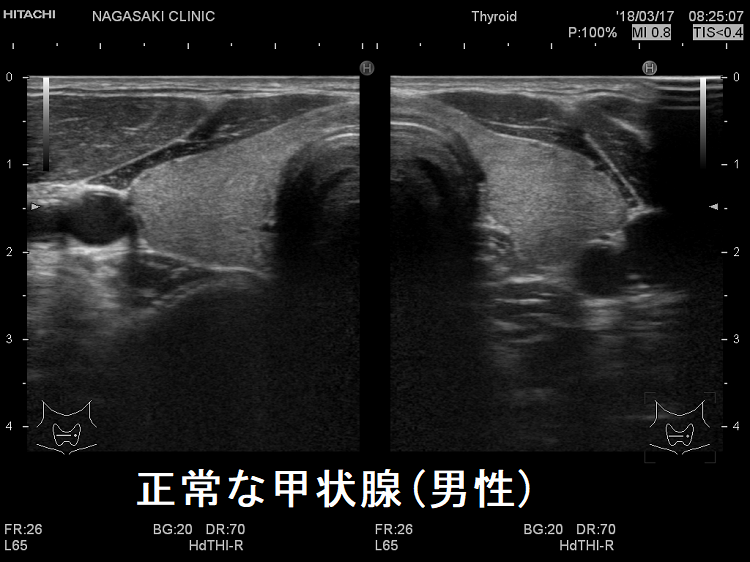

「正常な甲状腺」と診断するには、どうすればよいか?そもそも、「正常な甲状腺」とはどのような甲状腺を指すのでしょうか?「異常のあるもの」を「異常」と言うのは簡単な事ですが、「異常が無い」と断言するのは意外と難しい事があります。

JABTS(日本乳腺甲状腺超音波医学会)の定義では、

- 甲状腺の病気がなく、

- (採血で)甲状腺ホルモンの値が正常

- 超音波検査で異常が認められない

ものが「正常な甲状腺」です。すなはち、甲状腺エコー(甲状腺超音波検査)しなければ、「正常な甲状腺」と診断できない事になります。1. 2.は簡単ですが、3.は甲状腺エコー(甲状腺超音波検査)に精通した専門医の技術が必要になります。